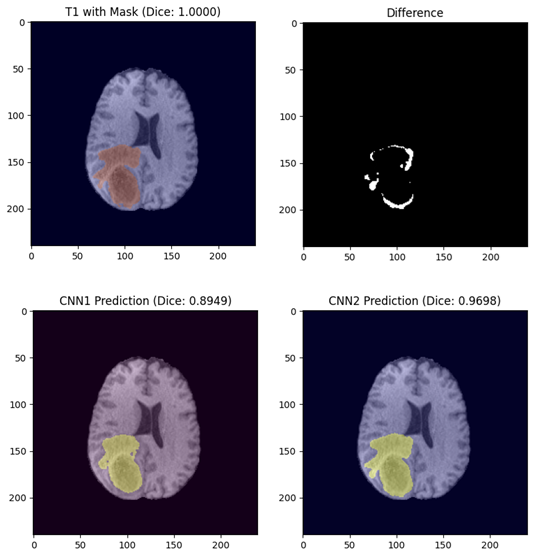

Brain Tumor Segmentation Notebook

Brain Tumor Segmentation Results Preview

A Jupyter notebook for Deep Learning assignment to detect brain tumors using MRI sequences.

This notebook features two Convolutional Neural Networks (CNN) with different approaches and compare their performance over a given dataset using the dice coefficient metric.